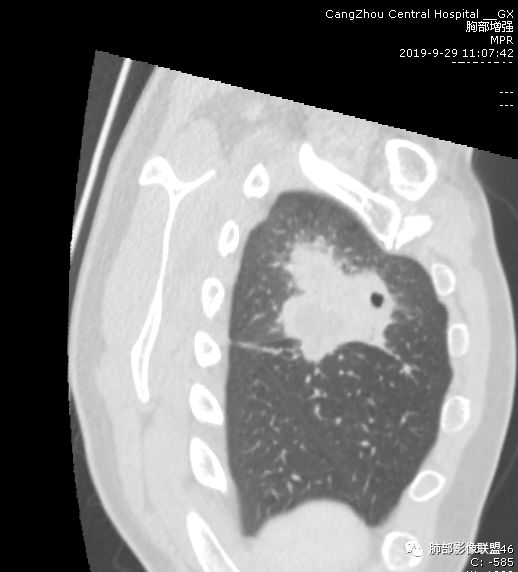

右肺上叶分叶状肿块(冠状位尤为明显),内见液化坏死,支气管截断,收缩力强,周围有片状影,右侧腋窝及纵隔淋巴结增大,增强有强化,定性恶性病变,脓肿形态及临床症状不符,暂排除。

右肺上叶不规则团块影,边缘欠清晰,增强扫描坏死区边界清晰,水平裂牵拉上移,考虑机化性肺炎并脓肿,鉴别:结核、肺癌。

首先病灶示:跨尖、后、前三段,局部突入中叶;大家理解一下:是不是光滑的地方有叶裂,毛糙的地方没叶裂。

这个病变两侧受叶裂的局限,中央没有,如果是穿透叶裂的是否边缘也毛糙?事实上这叶裂边缘的叶裂是很光滑的,我倾向于这个是局部叶裂有缺陷;就是从缺陷处进来有病灶的本色:边缘毛糙;附近叶裂的阻挡,边缘光滑;既然怀疑是局部的缺陷就对良恶性没价值。

中央太突兀了,有道理;如果恶性侵犯也不会这么突兀,所以可能是有缺陷或薄弱的地方;

恶性侵犯,整体都会毛糙

对,这个病灶周围胸膜没有膨隆或占位效应,会不会病变以收缩为主;如果有缺陷,这种良恶性都可以,两侧胸膜没有膨隆,也不能说排除恶性;如果膨隆,恶性可能性大,但是也可以被阻挡。

周围GGO,不是远端;

而且这个病灶明显跨段,属于外围的病变,不受某一段支气管的局限;

宽基底,胸膜增厚

炎性病变一定有

但是深分叶,坏死部分内壁不清

近端支气管堵塞

肺门淋巴结肿大

恶性一定不能除外

建议治疗后复查或穿刺,警惕恶性;

为啥说不能排除,而不是直接下恶性?因为有感染的同时很多征象都不是很确定;万一感染掩盖了,或者感染某个过程造成的假象,我们直接下诊断,就没退路了,我觉得应该从写报告的角度去读最合适。

跨叶病灶有很多种思路,跨叶的病灶多是炎性的,炎性病变沿着胸膜直接蔓延到对侧;恶性肿瘤也有,但是不多,相对比例低,但是恶性肿瘤目前的观点,有两大派:

第一种有直接侵犯过去的;叶间胸膜有2层脏层胸膜,间隔胸膜腔,侵及对侧常会形成胸水,胸膜或多或少都有改变。

第二种是局部叶裂畸形或发育不全、有缺陷,病灶经缺陷处侵犯蔓延,事实上叶裂缺并非少见,影像观察应当结合冠矢状位。

假如一个病灶直接跨越胸膜侵犯过来,应该边缘都很毛糙,不应该是最突出的地方毛糙,应该是逐步毛糙过去的,充其量越到外面毛糙越少;但事实上今天这个病变是一个很突兀的毛糙,突然间嘎然而止的毛糙;所以这个提示应该是从缺陷处跨过来的;还有今天的这个病例,病灶跨叶的部分对附近的胸膜是推移的,附近的胸膜还是很光滑,但是跨叶的病灶区很毛糙,提示跨叶部分存在胸膜缺陷可能;一般来说恶性肿瘤直接侵犯到对侧还是少的,如果这个地方你怀疑有缺陷,跨胸膜在诊断良恶性价值就不大了。